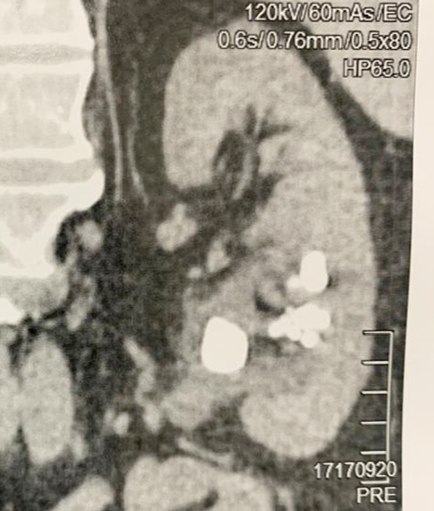

Caso do Mês: Set/2022: Tratamento de Cálculos Renais pela técnica de Dusting

Tratamento de Cálculos Renais pela técnica de Dusting com Thulium Fiber Laser

Litíase Renal - Thulium

-62 anos, masc.

-Antecedente de cirurgia percutânea há 8 anos

-Dor lombar esquerda recorrente

Imagem Inicial e final: